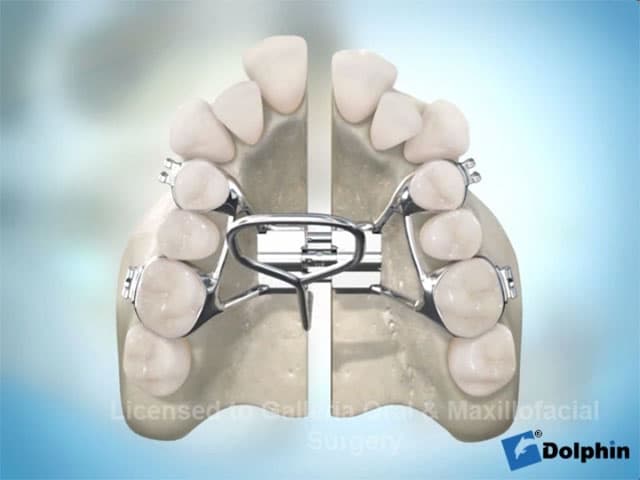

Computer-planned orthognathic surgery to correct jaw misalignment, restore bite function, and achieve facial harmony. Dr. Antipov treats underbites (Class III malocclusion), overbites (Class II malocclusion), open bites, crossbites, facial asymmetry, and obstructive sleep apnea. Procedures include Le Fort I osteotomy (single-piece and 3-piece), bilateral sagittal split osteotomy (BSSO), genioplasty (chin repositioning), maxillomandibular advancement, and double jaw surgery. Every case uses 3D virtual surgical planning for millimeter-precise results.

Explore detailed 3D animations of dental implant placement, jaw surgery, wisdom teeth extraction, and more. Understanding your procedure helps you feel confident and prepared.